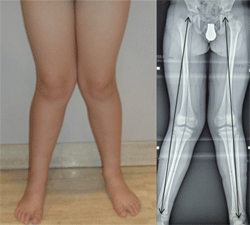

Durante su infancia y adolescencia, Miguel Ángel padeció diversos problemas además de su discapacidad visual. Problemas como tener los pies planos y el síndrome de Genu Valgo, que se solucionaron con muchos años de zapatos ortopédicos y aparatos de hierro para enderezar sus rodillas (como los que llevaba Forrest Gump).

Imagen que muestra las piernas de un niño con las rodillas torcidas hacia adentro